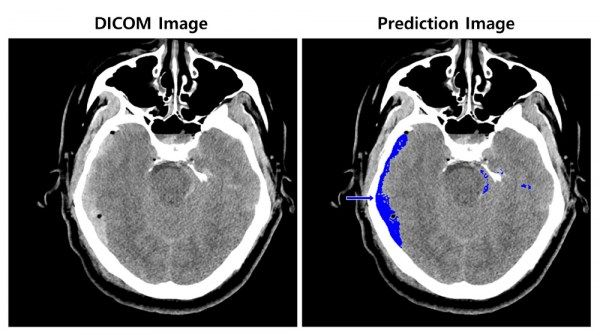

Giải pháp do công ty SK C&C phát triển, phân tích hình ảnh chụp CT não trong vòng vài giây với AI, thông báo cho nhân viên y tế về vị trí chảy máu và bất kỳ bất thường nào với độ chính xác hơn 97%.